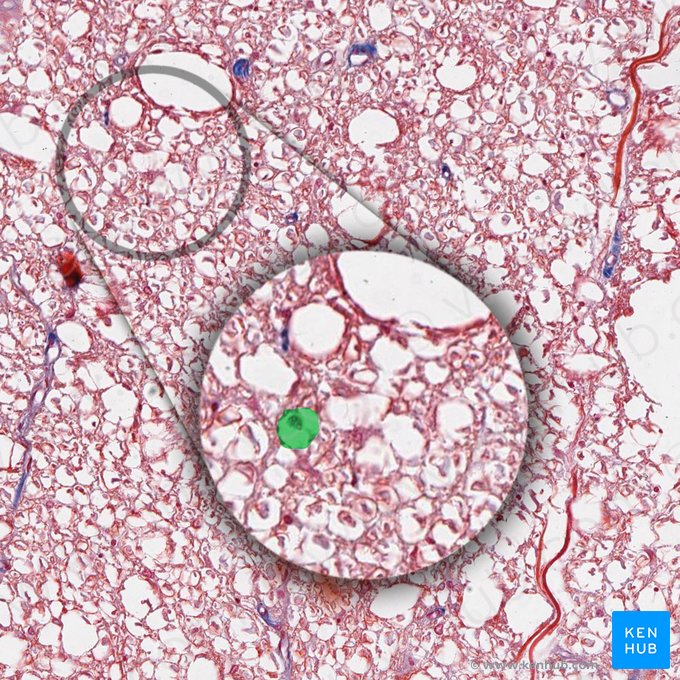

The spinal cord is divided into a central, gray matter and a peripheral, white matter. The gray matter is the butterfly-shaped central part of the spinal cord and is comprised of neurons and synapses. It is divided into anterior, lateral and posterior horns. The anterior horn houses the motor neurons, while the posterior horn receives sensory information.

White matter consists primarily of myelinated nerve fibers and is organized into ascending (sensory) and descending (motor) tracts. The fiber tracts are organized into an anterior funiculus, a lateral funiculus and a posterior funiculus.